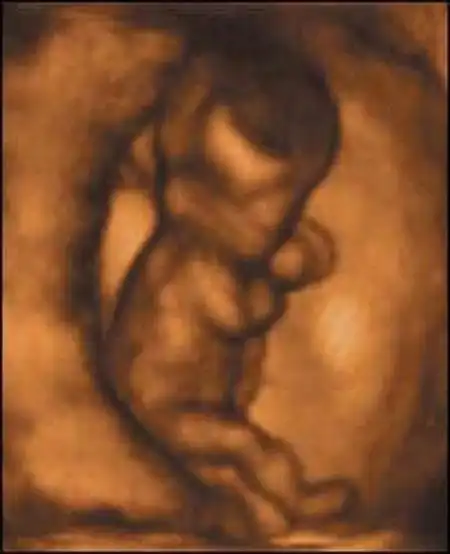

С 9-й недели начинается плодный период. Особенно интенсивно развивается печень. До 20-й недели она играет роль главного кроветворного органа ребенка. Активно растут мышцы на руках и ногах. Плод в состоянии двигаться, но пока хаотично, поскольку мозжечок еще не созрел.

На 10-й неделе лицо полностью сформировалось, но глаза еще закрыты. Кишечник удлиняется и закручивается в петли. Плод уже может глотать. Оба полушария головного мозга уже есть, начинает развиваться мозжечок.

На 11-й неделе продолжается окостенение скелета. Развиваются эндокринные железы и лимфоузлы. Сердце бьется с частотой 130-150 ударов в минуту. 9-сантиметровый ребенок двигает головой, руками, ногами, сжимает кулачки, поворачивает голову и даже пробует сосать свой палец.